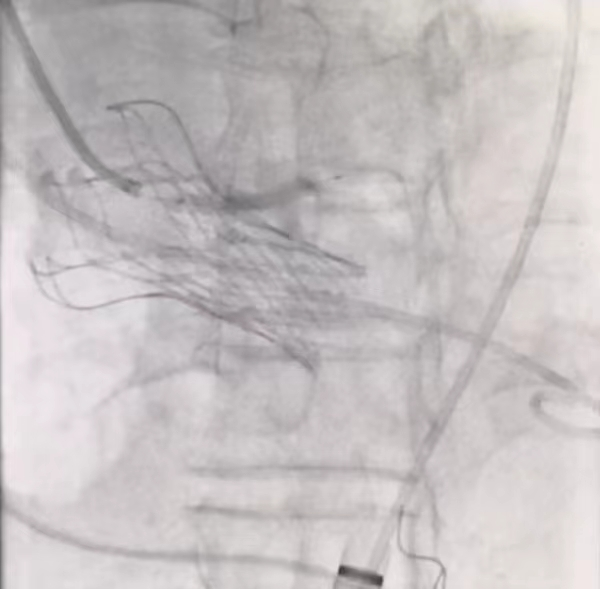

3,开窗支架定位造影

4,开窗支架释放过程